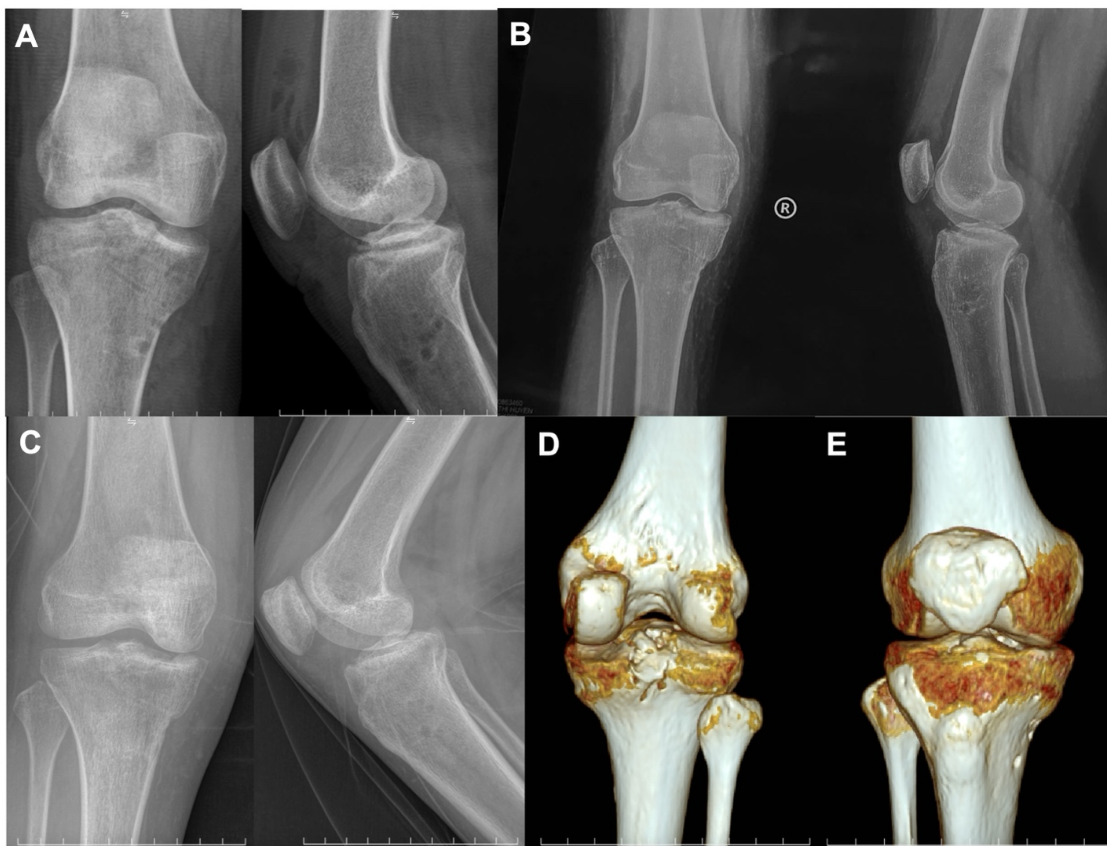

On examination, the right knee demonstrated mild swelling and restricted ROM due to pain. The Lachman’s test and anterior–posterior drawer tests were positive, indicating combined cruciate ligament instability. No associated neurovascular compromise was detected. Radiographic and CT evaluation confirmed completely displaced simultaneous tibial avulsion fractures of the ACL and PCL, with no associated tibial plateau fracture or additional osseous injury (Figure 1). Based on the clinical and radiologic findings, a diagnosis of completely displaced simultaneous ACL and PCL tibial avulsion fractures was established.

Immediate postoperative radiographs demonstrated anatomic reduction of the avulsed fragments (Fig 4A). Follow-up imaging at 1 month confirmed maintenance of stable fixation (Fig 4B). Radiographs and CT at 3 months revealed complete osseous union with preservation of anatomic alignment (Fig 4C, D, E). At 6 months postoperatively, the patient achieved a knee range of motion from 0° to 150°, with negative Lachman’s test and anterior–posterior drawer tests. Functional evaluation demonstrated an objective IKDC grade A, a subjective IKDC score of 100, and a Lysholm score of 100. The patient returned to normal daily activities without pain or residual instability.